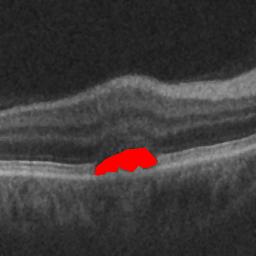

The qualitative results of the proposed system is shown in the Fig. 3. The detection task is evaluated using Area Under the Curve(AUC) metric and the segmentation task is evaluated using Dice Coefficient(DC) metric and the results are presented in Table1

| (d) De-noised OCT slice | (e)Predicted fluid region | (f)Manual fluid segmentation |

|

|

|

| (g) De-noised OCT slice | (h)Predicted fluid region | (i)Manual fluid segmentation |